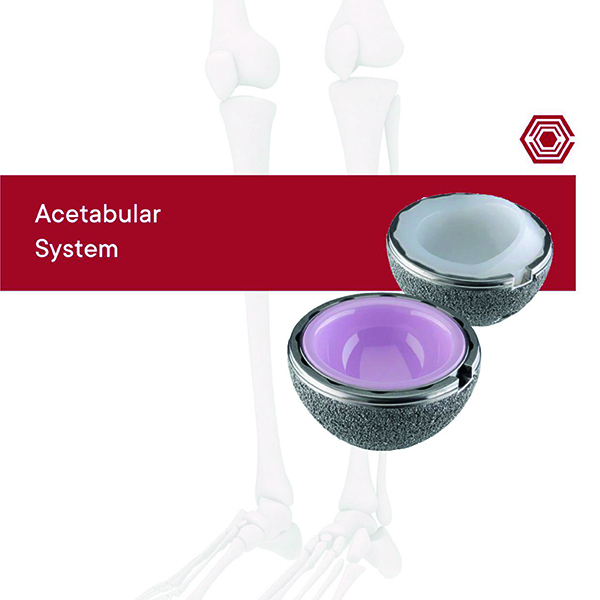

Acetabular System

Akif Kaya Aybek

Norm Akademi

- Surgical Techniques

- Implant Types

- Instrument Types